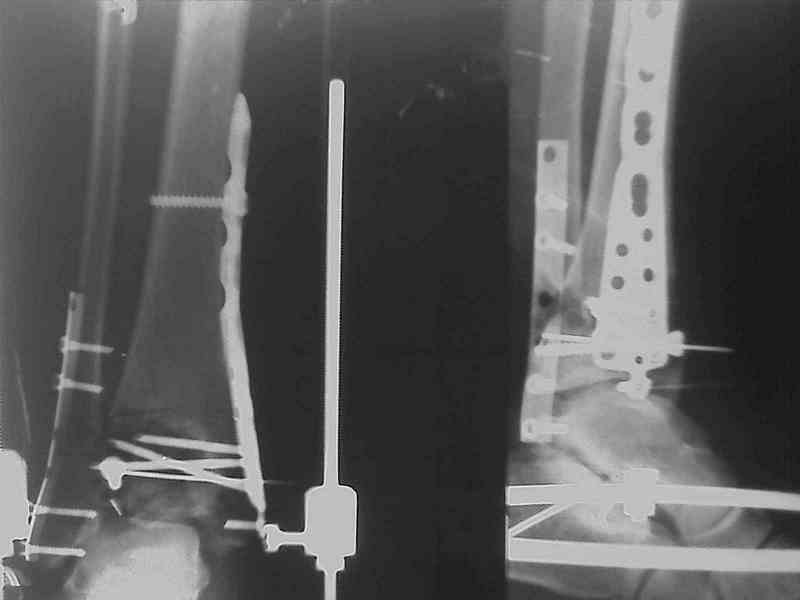

Снова приветствую вас, коллеги. К моменту вступления в обсуждение аксакалов, операция была, увы, выполнена(31.10.07.) Начали с доступа к наружной лодыжке, произвели ее фиксацию спицами, развернули кусок заднего края, наложили дистрактор, затем произвели дистракцию, фиксацию спицами дистального эпиметафиза б/бк,Рентгено-контроль. синтез наружной лодыжки 1/3пластиной. из двух коротких разрезов сформирован канал под медиальную тибиальную пластину LCP. Края ран ушиты без натяжения. Прочувствовать жесткость фиксации винтами с угловой стабильностью не удалось, поэтому дистрактор оставлен на энное время.

На представленных R-снимках не окончательный вид после остеосинтеза. Дистальная опора давила на стопу, пришлось ее сместить проксимально, в рез-те чего, она закрыла щель сустава, последние снимки не информативны.

2. Второе. Следует обязательно усилить фиксацию: спицы через передний отдел стопы и пяточную кость, вторая спица через проксимальное кольцо и 1-2 стержня в проксимальный отломок б/б кости. Сроки фиксации до 8 недель. Аппаратом можно устранить, кажется, появившийся вальгус. В подобных ситуациях лучше ведут себя стержни, которыми можно сопоставить и сдавить лодыжки и задний край б/б кости. Привожу случай восстановления голеностопного сустава спустя 2,5 мес.(этап лечения) после травмы со стержнями.